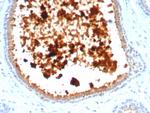

Mammaglobin (SCGB2A2) (Breast Cancer Marker) Antibody in Immunohistochemistry (Paraffin) (IHC (P))

图: 1 / 3

Mammaglobin (SCGB2A2) (Breast Cancer Marker) Antibody (4250-RBM11-P1ABX) in IHC (P)

Formalin-fixed, paraffin-embedded human lactating breast stained with Mammaglobin Recombinant Rabbit Monoclonal Antibody (MGB/4811R). {{ $ctrl.currentElement.advancedVerification.fullName }} 验证信息 View more